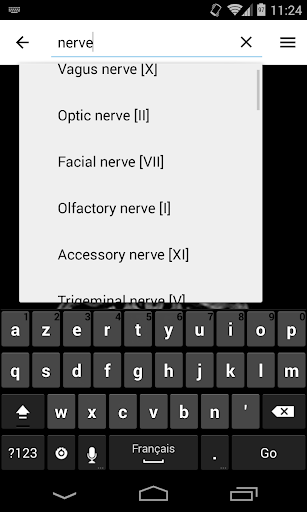

* اعثر على الأجزاء التشريحية الخاصة بك بسهولة أكبر بفضل ميزة البحث الجديدة والأكثر سهولة وقوة

* تحسين أداء البحث عن البنية التشريحية